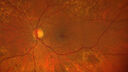

BRAO - plaques in vessels - GIF video of FA3 views78 year old female with vision loss for 1 week and old macular scar. Images show BRAO with plaques and FA shows occlusion.Oct 13, 2025